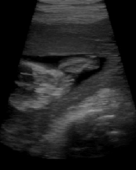

3. 4DUS – 4-Dimensionaler Ultraschall

4DUS – 4-Dimensionaler Ultraschall

Die räumliche Auflösung des Herzens bei gängigen in-vivo Ultraschall Anwendungen ist aufgrund von Bewegungsartefakten und Positionierungsfehlern ...